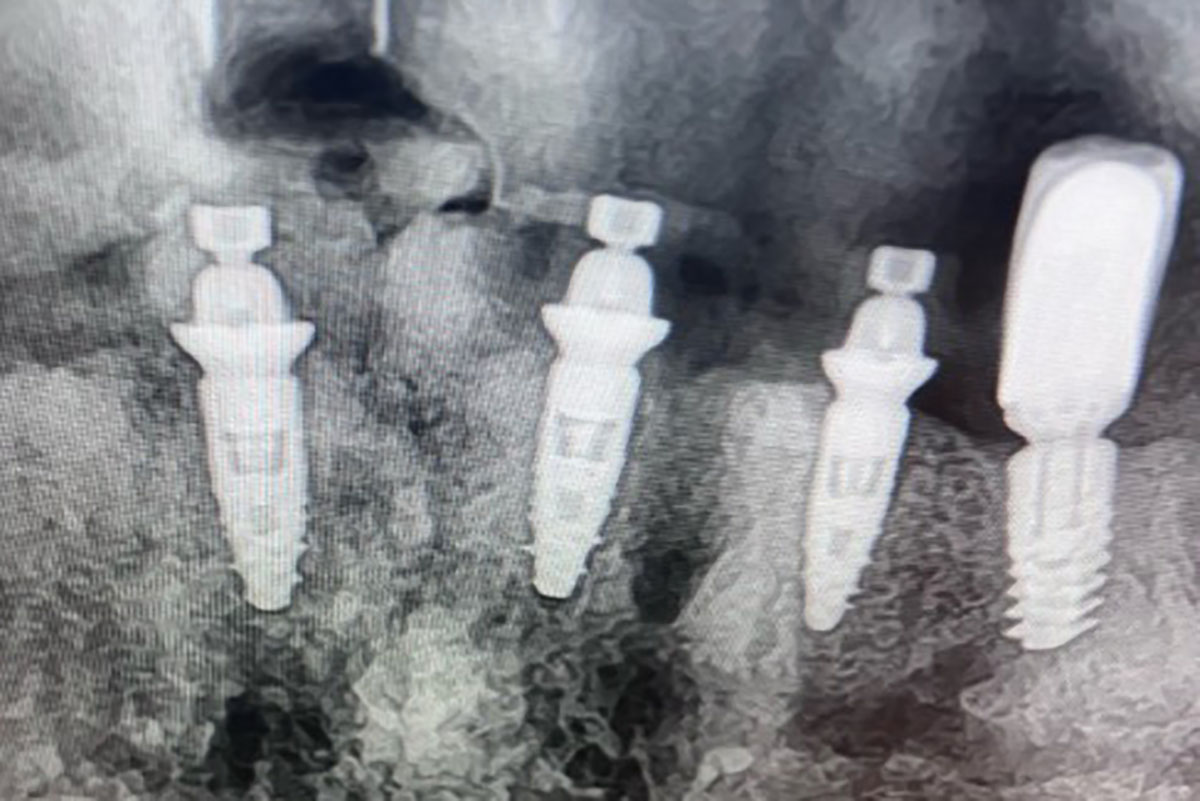

Extraction – Implantation immédiate après kyste infecté : résultat esthétique à 14 mois

Patiente de 40 ans adressée pour une infection chronique au niveau d’une incisive maxillaire. L’examen clinique mettait en évidence une fistule vestibulaire importante en regard de la dent concernée, sans mobilité associée malgré une atteinte infectieuse avancée. L’objectif thérapeutique était double : traiter l’infection et le kyste de manière complète,